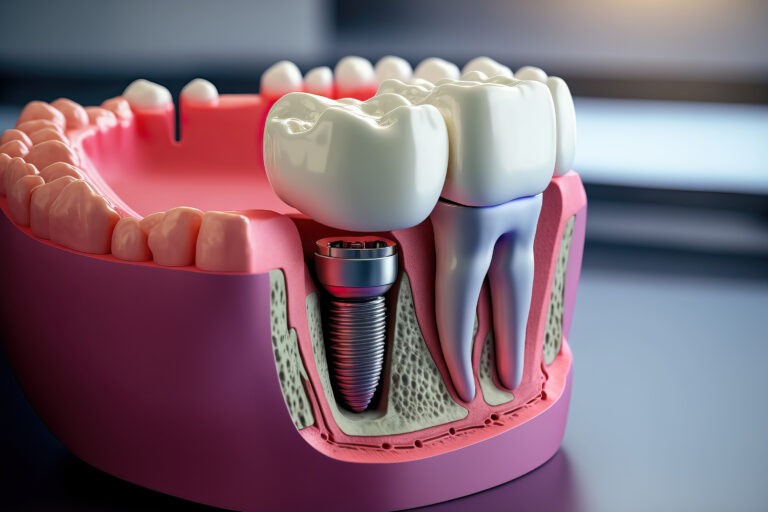

Leczenie kanałowe jest jedną z najczęściej wykonywanych procedur w gabinetach stomatologicznych. Procedura ta polega na usunięciu zakażonej lub uszkodzonej miazgi z wnętrza zęba, a następnie wypełnieniu powstałej przestrzeni specjalnym materiałem. Leczenie kanałowe pozwala uratować ząb, który w przeciwnym razie musiałby…